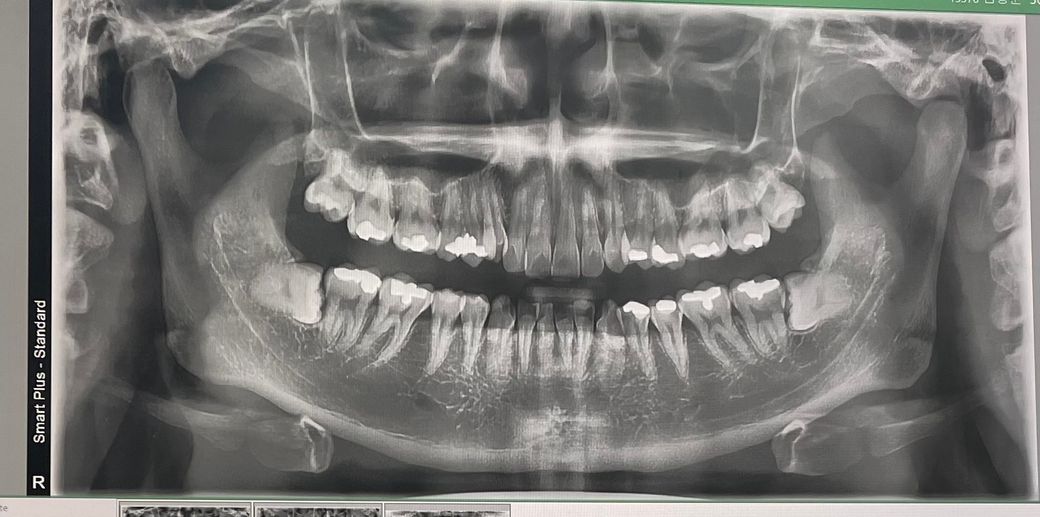

치과에서 아말감 떼운곳 안쪽이 충치가 심해서 신경치료해야한다 합니다 해야할까요? 다른 병원 가봐야할까요?

일상에선 안 아픈데 왼쪽 아래 치아에 치실도중 특정부분을 건드릴때 충치처럼 살짝 시큰해 x레이 찍어보았습니다 신경치료 및 크라운 비용 50씩 두곳 해야한다는데 다른 곳과 비교해봐야할까요? 치아 엑스레이 첨부합니다

사진상에서 보기에는 충치의 진행정도로 보면 신경치료 가능성이 높아보입니다. 치료받는 게 좋겠습니다.

사진상으로 오른쪽아래 작은어금니가 충치가 많이 진행된거 같습니다 신경치료를 하시긴 하셔야될것같습니다.

엑스레이상 충치 진단이 맞아보입니다 그 중 왼쪽 아래 두번째 어금니는 충치가 꽤 깊고 클 수도 있어보입니다